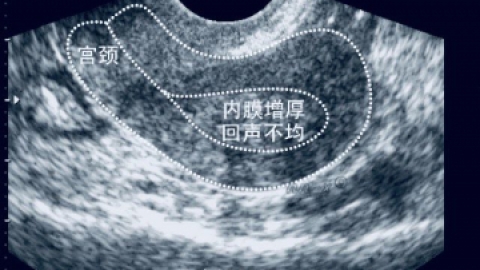

那么什么是子宫内膜增厚?子宫内膜的正常厚度是多少?因此,子宫内膜的厚度并不是一个固定的值,它会随着月经周期,而出现周期性变化。2、分泌期:黄体形成后,在孕激素作用下,子宫内膜呈分泌反应。此期内膜腺体更长,屈曲更明显。子宫内膜增厚呈海绵状。分泌晚期时,